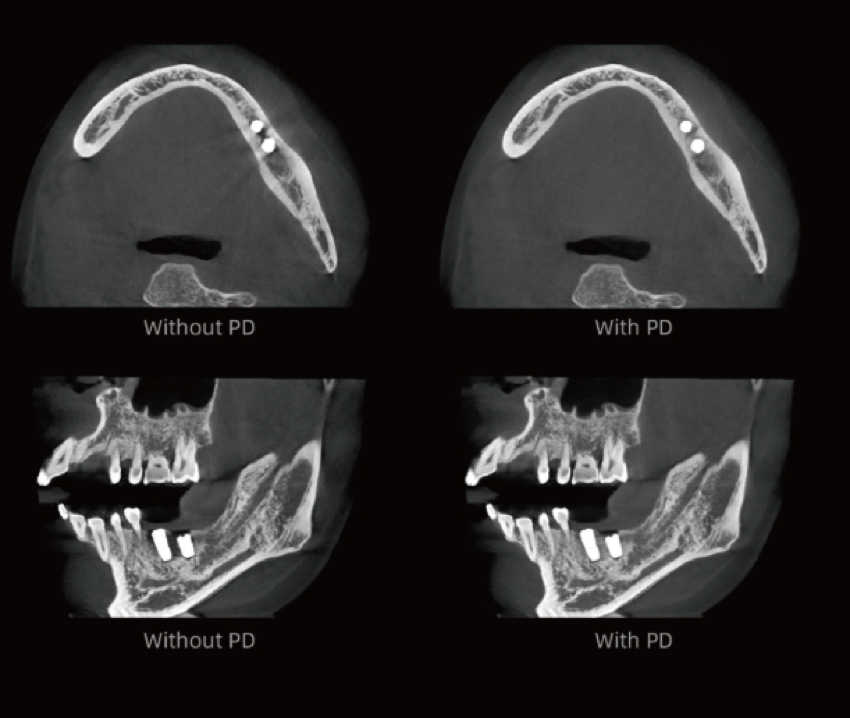

Algoritmo PD – Alta resolução espacial em TC até 2,8 lp/mm

Proporciona imagens com efeito de “textura natural”.

Previne eficazmente que pequenas lesões sejam ocultadas pela redução de ruído, reproduzindo com elevada fidelidade os detalhes do osso e dos tecidos moles.

Fornece aos clínicos informação diagnóstica mais precisa.